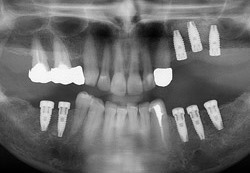

- Cas 2: vues panoramiques

APRES REHABILITATION 3 SECTEURS MOLAIRES